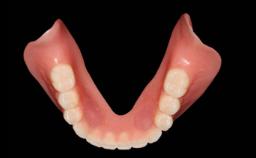

Prosthesis Type FDP

Defining Characteristics Up to three missing teeth to be replaced with an implant-borne restoration or restorations

Loading Protocol Conventional or early

Retention Screw-retained, with splinted implants Screw-retained, with splinted implants